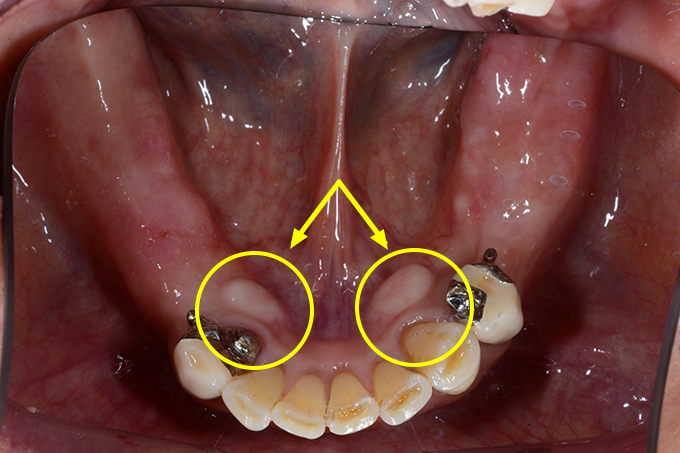

骨隆起って何?

下の写真の矢印部は、歯ぐきが膨らんで、触れると硬く骨ばっています。

ほとんどの方が気づかれてないです。中には、「えっ!?みんなあるんじゃないんですか?」

「歯ぐきが腫れてる感じがします」とおっしゃる方もおられます。

これは遺伝やかみ合わせ、強い咬合力などにより、骨が部分的に増殖したもので、上アゴの中央や下アゴの内側(ベロ側)にできることが多いです。病的なものではありません。

ただ、入れ歯を作るのに障害になることがあります。(お悩みの方はこちら)

これがある方は、歯ぎしり、食いしばり、かみしめを疑ってください。